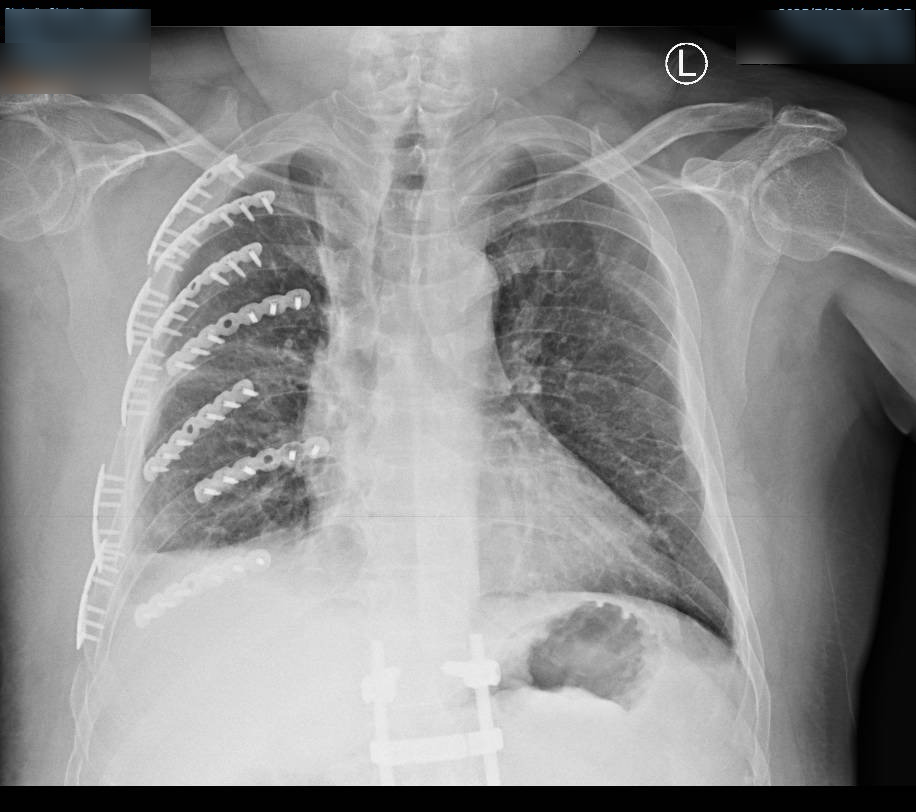

▲國道工作人員撿拾布鉤繩遭到遊覽車釀全身多處粉碎性骨折。(圖/彰化醫院提供)

送醫後檢查發現,陳男不僅有8根肋骨斷成14截,更出現致命性的「連枷胸」,吸氣時胸腔會反常凹陷;右手橈骨粉碎性骨折碎成10多塊,骨盆腔也嚴重受損。

彰化醫院胸腔創傷中心主任林聿騰指出,透過3D胸廓重組影像定位,僅開2個小傷口就用鈦合金骨板固定變形胸腔。骨科醫師陳柏辰接力以鋼板處理粉碎的右手橈骨。歷經馬拉松式手術,陳男總算脫離痛苦。歷經接連手術後,已轉到一般病房,在家人照顧下的他說,手術前,再強的止痛劑也無法止痛,經微創手術後,他才體會到可以自由呼吸是多麼美好的事。